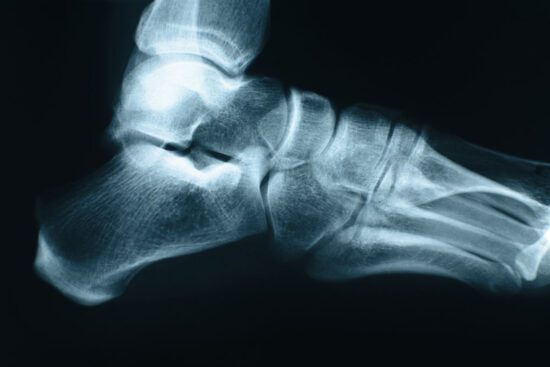

Writing in Seminars in Musculoskeletal Radiology, 2 European experts review typical anamnestic/clinical findings, epidemiology and risk factors, imaging characteristics, and findings at typical locations of bone stress injuries in the foot and ankle that may help guide treatment strategy and patient recovery. Bone stress injuries (BSIs) are a frequent finding in athletes, particularly of the foot and ankle. A BSI is caused by recurring microtrauma to the cortical or trabecular bone exceeding the repair capacity of normal bone. The most frequent fractures at the ankle are low risk, characterized by a low risk for nonunion. These include the posteromedial tibia, the calcaneus, and the metatarsal diaphysis. High-risk stress fractures have a higher risk for nonunion and need more aggressive treatment. Examples are the medial malleolus, navicular bone, and the base of the second and fifth metatarsal bone. They note that imaging features depend on the primary involvement of cortical versus trabecular bone and that conventional radiographs may remain normal up to 2 to 3 weeks. For cortical bone, early signs of BSIs are a periosteal reaction or the “gray cortex sign,” followed by cortical thickening and fracture line depiction. In trabecular bone, a sclerotic dense line may be seen. In their opinion, magnetic resonance imaging enables early detection of BSIs and can differentiate between a stress reaction and a fracture.